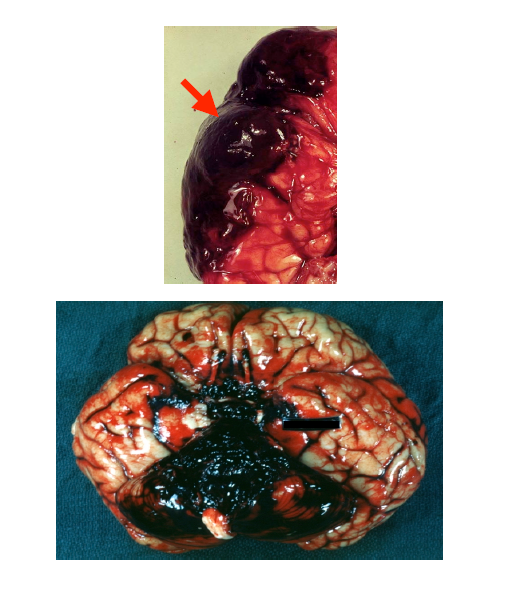

What study should be ordered on a patient with a similar presentation (before autopsy)?

Angiography.

Subarachnoid Hemorrhage

• Caused by aneurysmal rupture ortrauma

• Overlying the blood is the arachnoid membrane (arrow).

What was the mechanism of injury for this patient?

Area of hemorrhagic necrosis from cerebral contusion.

– Usually affects the crest of gyri.

– Frequently seen in subfrontal and anterior temporal lobes as the base of the brain slides over the irregular skull base

• Blood is removed by macrophages leaving an irregular tan discoloration.